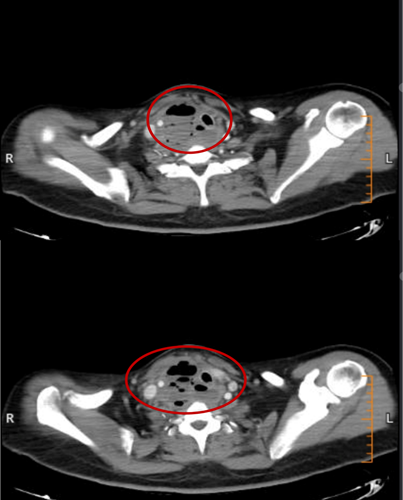

2月15日与20日,当整座城市沉浸在辞旧迎新的欢声笑语中,两位病情凶险的颈部深部脓肿患者先后被推入耳鼻咽喉头颈外科。他们都有多年糖尿病病史,春节期间饮食不规律、作息紊乱、血糖波动大,让原本隐匿的感染如野火般迅速蔓延。其中一位患者的感染已突破颈部间隙,如藤蔓般向下侵入纵隔区域——那里是心脏、大血管、气管的“交通枢纽”,是人体最脆弱的生命禁区之一。CT影像上,脓肿中密布的气腔像一个个危险的信号,气管被严重受压,每一次呼吸都变得艰难。文献数据冰冷而沉重:颈深部脓肿并发下行性纵隔炎,病死率高达40%~70%。时间,从未如此紧迫。

患者甲CT示:颈部及纵隔脓肿,脓肿中含有多个气腔

患者乙CT示:颈部咽后间隙—右侧咽旁间隙—右侧颈动脉间隙脓肿